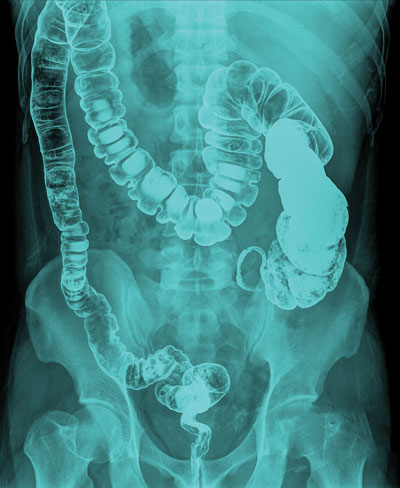

For the upper gastrointestinal study it is called barium meal or barium meal with follow through if it is required to visualize the small intestines. For the lower gastrointestinal study, it is called barium enema.

For barium enema: to observe the large bowels to look for ulcers, benign tumours (polyps, for example), cancer, or signs of certain other intestinal illnesses.

Barium enema

You will be positioned on your side on the x-ray table.

A rectal tube is then introduced into the rectum.

The radiologist or the diagnostic radiographer will introduce a mixture of barium and water into your colon through the tube.

Air may also be injected through the tube to help the barium thoroughly coat the lining of the colon.

You may be repositioned frequently to enable the radiologist and/or the diagnostic radiographer to capture views of the colon from several angles. When images are taken, you will be asked to hold your breath to ensure clear pictures of your colon are recorded.

Once the x-ray images are completed, most of the barium is drawn back into a bag, and the patient is directed to the washroom to expel the remaining barium and gas.

The examination usually takes about 30 to 60 minutes.